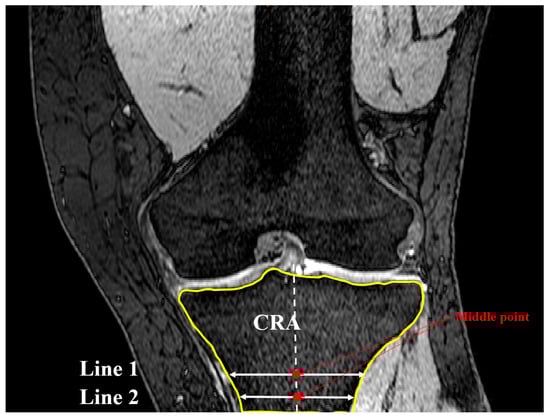

2.2. Coronal Tibial Slope Measurement Method

2.3. Concavity Zone